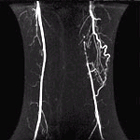

TRICKS - Angiographic Imaging - Signa EXCITE HD 1.5T

Tricks uses an intricate method of temporal sampling and complex data recombination to give very sharp images of arteries.